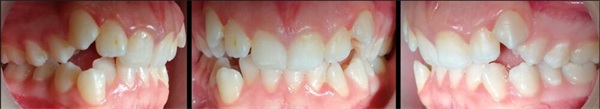

The Fastbraces Technology bracket systems have reduced orthodontic treatment durations to as little as 60–90 days. The case presented here (Figs. 1–5) is a 16-year-old female with a Class I occlusion on both sides, moderate crowding, and an open bite tendency. Interarch vertical elastics were used throughout the treatment.

Fig. 1: Case presented